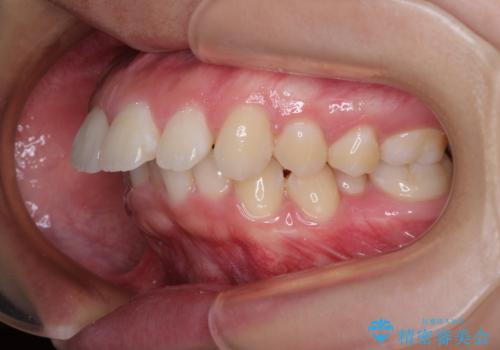

- 上顎前歯が飛び出していて唇がうまく閉じられないとのことで来院された患者様です。

くちばしのように前歯が突出していたため、口元を積極的に引っ込めるために、上下左右の小臼歯4本を抜歯することとしました。

また、上顎歯列が下顎に対して前方位に位置していたため、補助装置を用いて上顎歯列を後方に移動させ、より積極的に口元を下げるようにしました。

上下正中位置を改善するため、左下はイレギュラーに第二小臼歯を抜歯しました。そのため治療期間の長期化が予想されましたが、2年半ほどで期待通りの歯列に仕上げることができました。